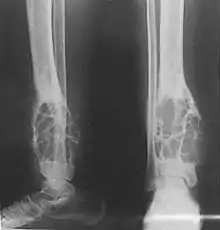

Patients typically present with swelling with or without pain. The slow-growing tumor predominantly arises in long bones in a subcortical location (95% in the tibia or fibula).[3] Most commonly, patients are in their second or third decade, but adamantinoma can occur over a wide age range.

Histologically, islands of epithelial cells are found in a fibrous stroma. The tumor is typically well-demarcated, osteolytic and eccentric, with cystic zones resembling soap bubbles.[2]

Diagnosis is on plain radiography, or CT scan